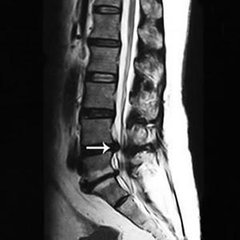

导读: 腰椎椎管狭窄症,是指由各种原因导致椎管的各径线缩短,压迫硬膜囊,脊髓或神经根,从而导致了相应的神经性功能障碍的一类疾病。

导读: 腰椎管狭窄是因为椎管各径线缩短,压迫硬膜囊,脊髓或神经根,最后引起相关的神经功能受到阻碍的病。在骨科临床较为常见,往往给患者带来腰部疼痛、活动受限、间歇性跛行的困扰,不能粗心大意,大家平时要做好防护。